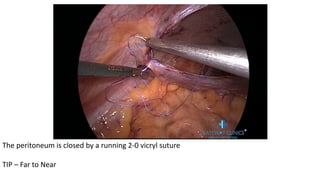

STEP 6 - The peritoneal closure

• The peritoneum is closed by a running suture using a 2-0 vicryl

• Look - Mesh is not exposed now to abdominal organs

The peritoneum is closed by a running 2-0 vicryl suture

TIP – Far to Near